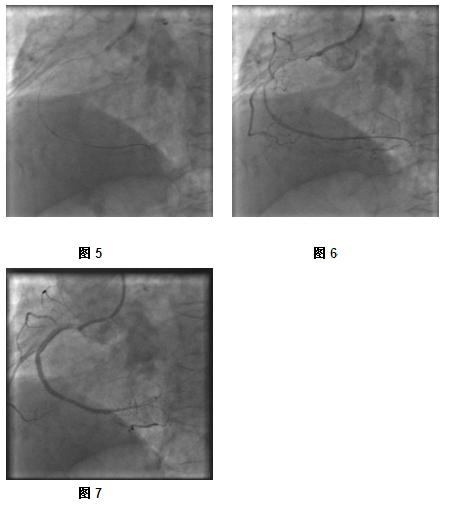

冠脉造影结果:前降支弥漫性斑块浸润伴狭窄钙化,最窄处狭窄达90%,可见前降支向回右冠提供侧枝;旋支弥漫性斑块浸润,近段狭窄80%,远段次全闭塞;右冠近段闭塞,自身桥侧枝向远端供血。(图1-3)

1、微导管支撑下 先后应用Runthrough及Pilot导丝通过病变处困难,前端疑进入假腔(图4)。